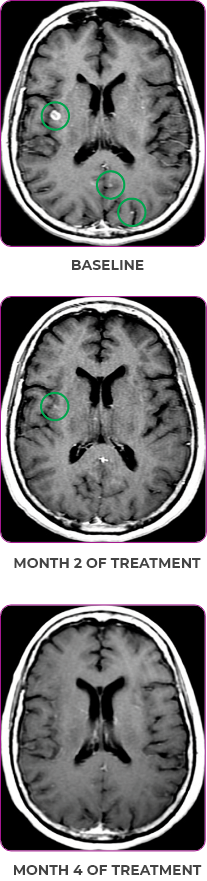

PATIENT CASE:

METASTATIC NSCLC1,a

- 30-year-old female

- Progression on first-line doublet chemotherapy

- PRa after 6 weeks of treatment with VITRAKVI® (larotrectinib)

- Complete clinical response achieved by 12 months with residual scarring

Response to VITRAKVI1

- Partial response and symptom improvement confirmed by chest X-rays after <1 month of treatment

- Imaging performed 6 weeks into treatment revealed considerable decrease in the size of both target lesions

- No treatment-related AEsa were reported

- Patient was symptom free and remained on VITRAKVI

Response in primary and metastatic lesions1

Lung imaging of primary tumors.

SCAN 1: LUNG

SCAN 2: LUNG AND BONE